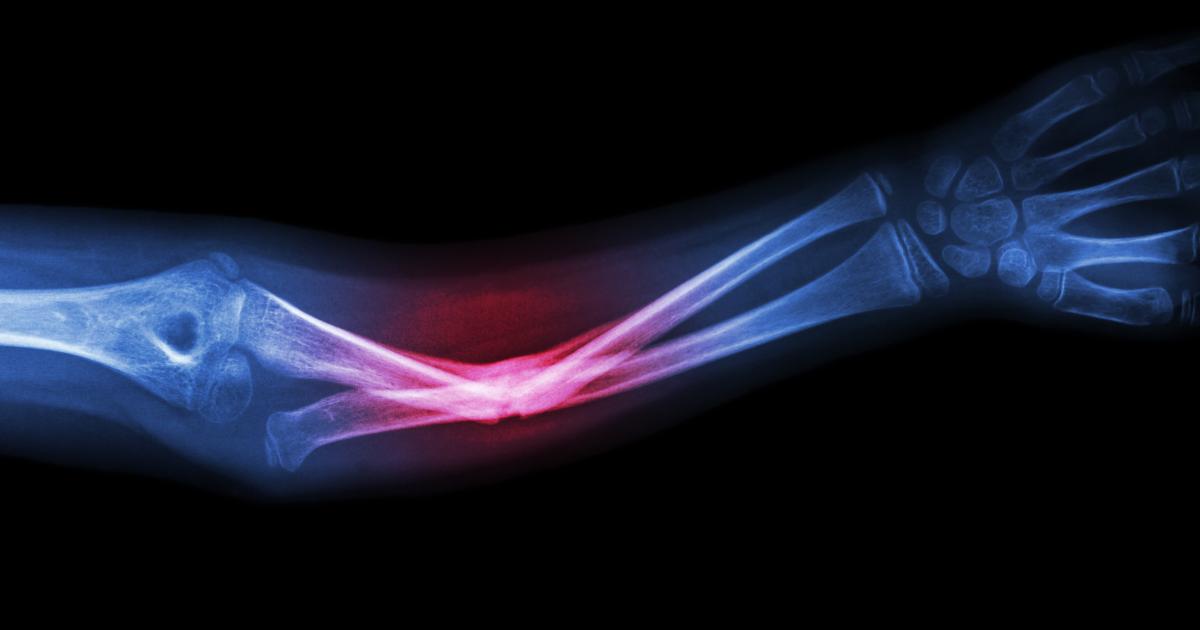

For the average baby not ultimately diagnosed with a moderate to severe form of Osteogenesis Imperfecta (OI)— a genetic disorder causing defects in quantity or quality of collagen— like Easton Elrod, fracturing a clavicle is not uncommon in a challenging vaginal birth. Due to positioning or a stuck shoulder or sometimes a large baby, this can occur. It is not an every day event, but happens enough that it is considered a consequence of normal birth trauma. When it does, the intervention is typically minimal as long as the bones are not displaced and impeding surrounding structures (a rare situation). Usually, the clinical course requires being aware of the area while clothing or moving the infant and being more gentle on that side as it heals -- all the while monitoring for continued symmetrical use and strength of the upper extremities.

Due to the wide spectrum of OI from mild to severe forms, in extreme cases the act of being born can be life-threatening. This brittle bone disease literally makes a newborn very fragile. In the extreme, it is not merely the pain of the many broken bones that is concerning but also what vital tissues they damage and organs they prevent from normally functioning. Crushing injuries can complicate the picture. Consider how challenging aerating the lungs can be if all the ribs are broken, for example.

Think about how a basic diaper change or a vigorous hug in a person with a more severe form of OI can elicit a fracture. Let alone recreational activities as a child ages.

The mainstay of treatment for OI includes medical, surgical and physical therapies designed to enhance function, prevent accidental trauma and provide supportive care. There is great variability in scope of disease. Having weaker bones is universal. Commonly, impaired growth is an issue as are bony deformities like bowing of the legs or curvature of the spine. Breathing can be affected, as can the heart, hearing and brittle nature of teeth.